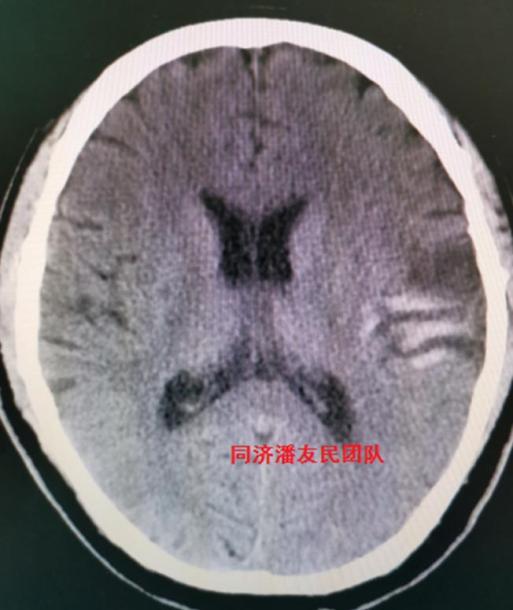

鉴于患者脑梗病情稳定,血压控制良好及家属意愿,最终确立保守治疗,待稳定后再手术治疗主动脉夹层。期间复查头部CT,脑梗病灶还合并了少量出血(图6)。